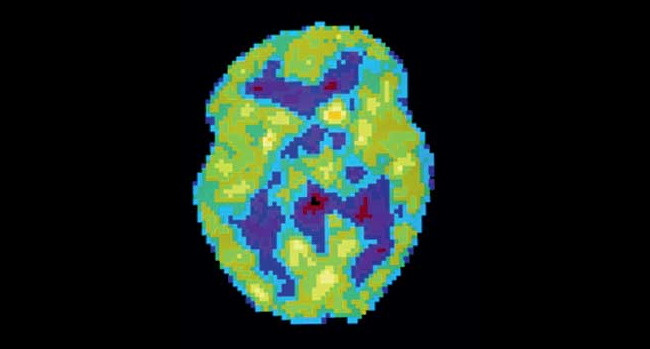

Активность мозга сильно различается не только во время бодрствования и сна — есть множество промежуточных состояний, которые можно различить во время позитронно-эмиссионной томографии.

НЕСПЯЩИЙ МОЗГ. Активность мозга в этой стадии (красные зоны на снимке) похожа на то, что происходит в REM-сне